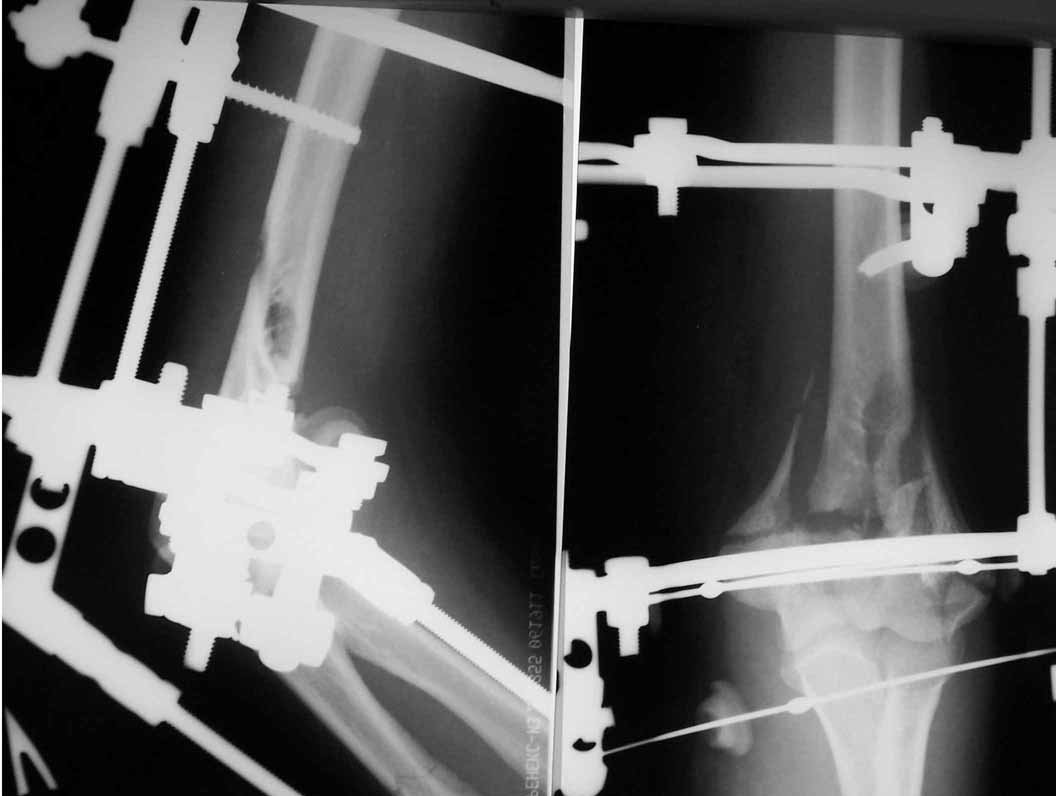

Alexander Artemiev 14 Сентябрь 2005, 16:19

Здравствуйте, коллеги.

МА> Трудно не согласиться с коллегами - только открыто и только пластинами

С коллегами не согласиться легко. Не обязательно открыто и не

обязательно пластинами или чем там ещё...

Снимки - во вложении.

Женщина 42 лет, операция через неделю после перелома.

Д-з - открытый перелом мыщелков со смещзением и локтевой кости

без смещения - падение с лошади.

До операции снимки не очень, тем более в гипсе.

Остеосинтез закрытый (если так можно выразиться), т.е. без

разрезов. Длительность операции - около 1,5 часа со студентом.

6 щелчков ЭОПом.